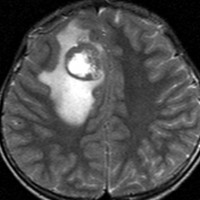

画像診断

- 悪性神経膠腫の特徴を示す画像所見です

- 腫瘍内出血,多房性のう胞をみることがあります

- 周囲脳浮腫が強いことが多いです

- MRIT1強調画像で低信号,T2で高信号

- ガドリニウムで部分的に増強されます,全く増強をみないものもあります

- 細胞密度が高いのでCTで高密度,MRSでcholineが高くなります

- 鑑別対象は,AT/RT,膠芽腫,退形成性上衣腫,他の胎児性腫瘍です,後頭窩であれば髄芽腫です